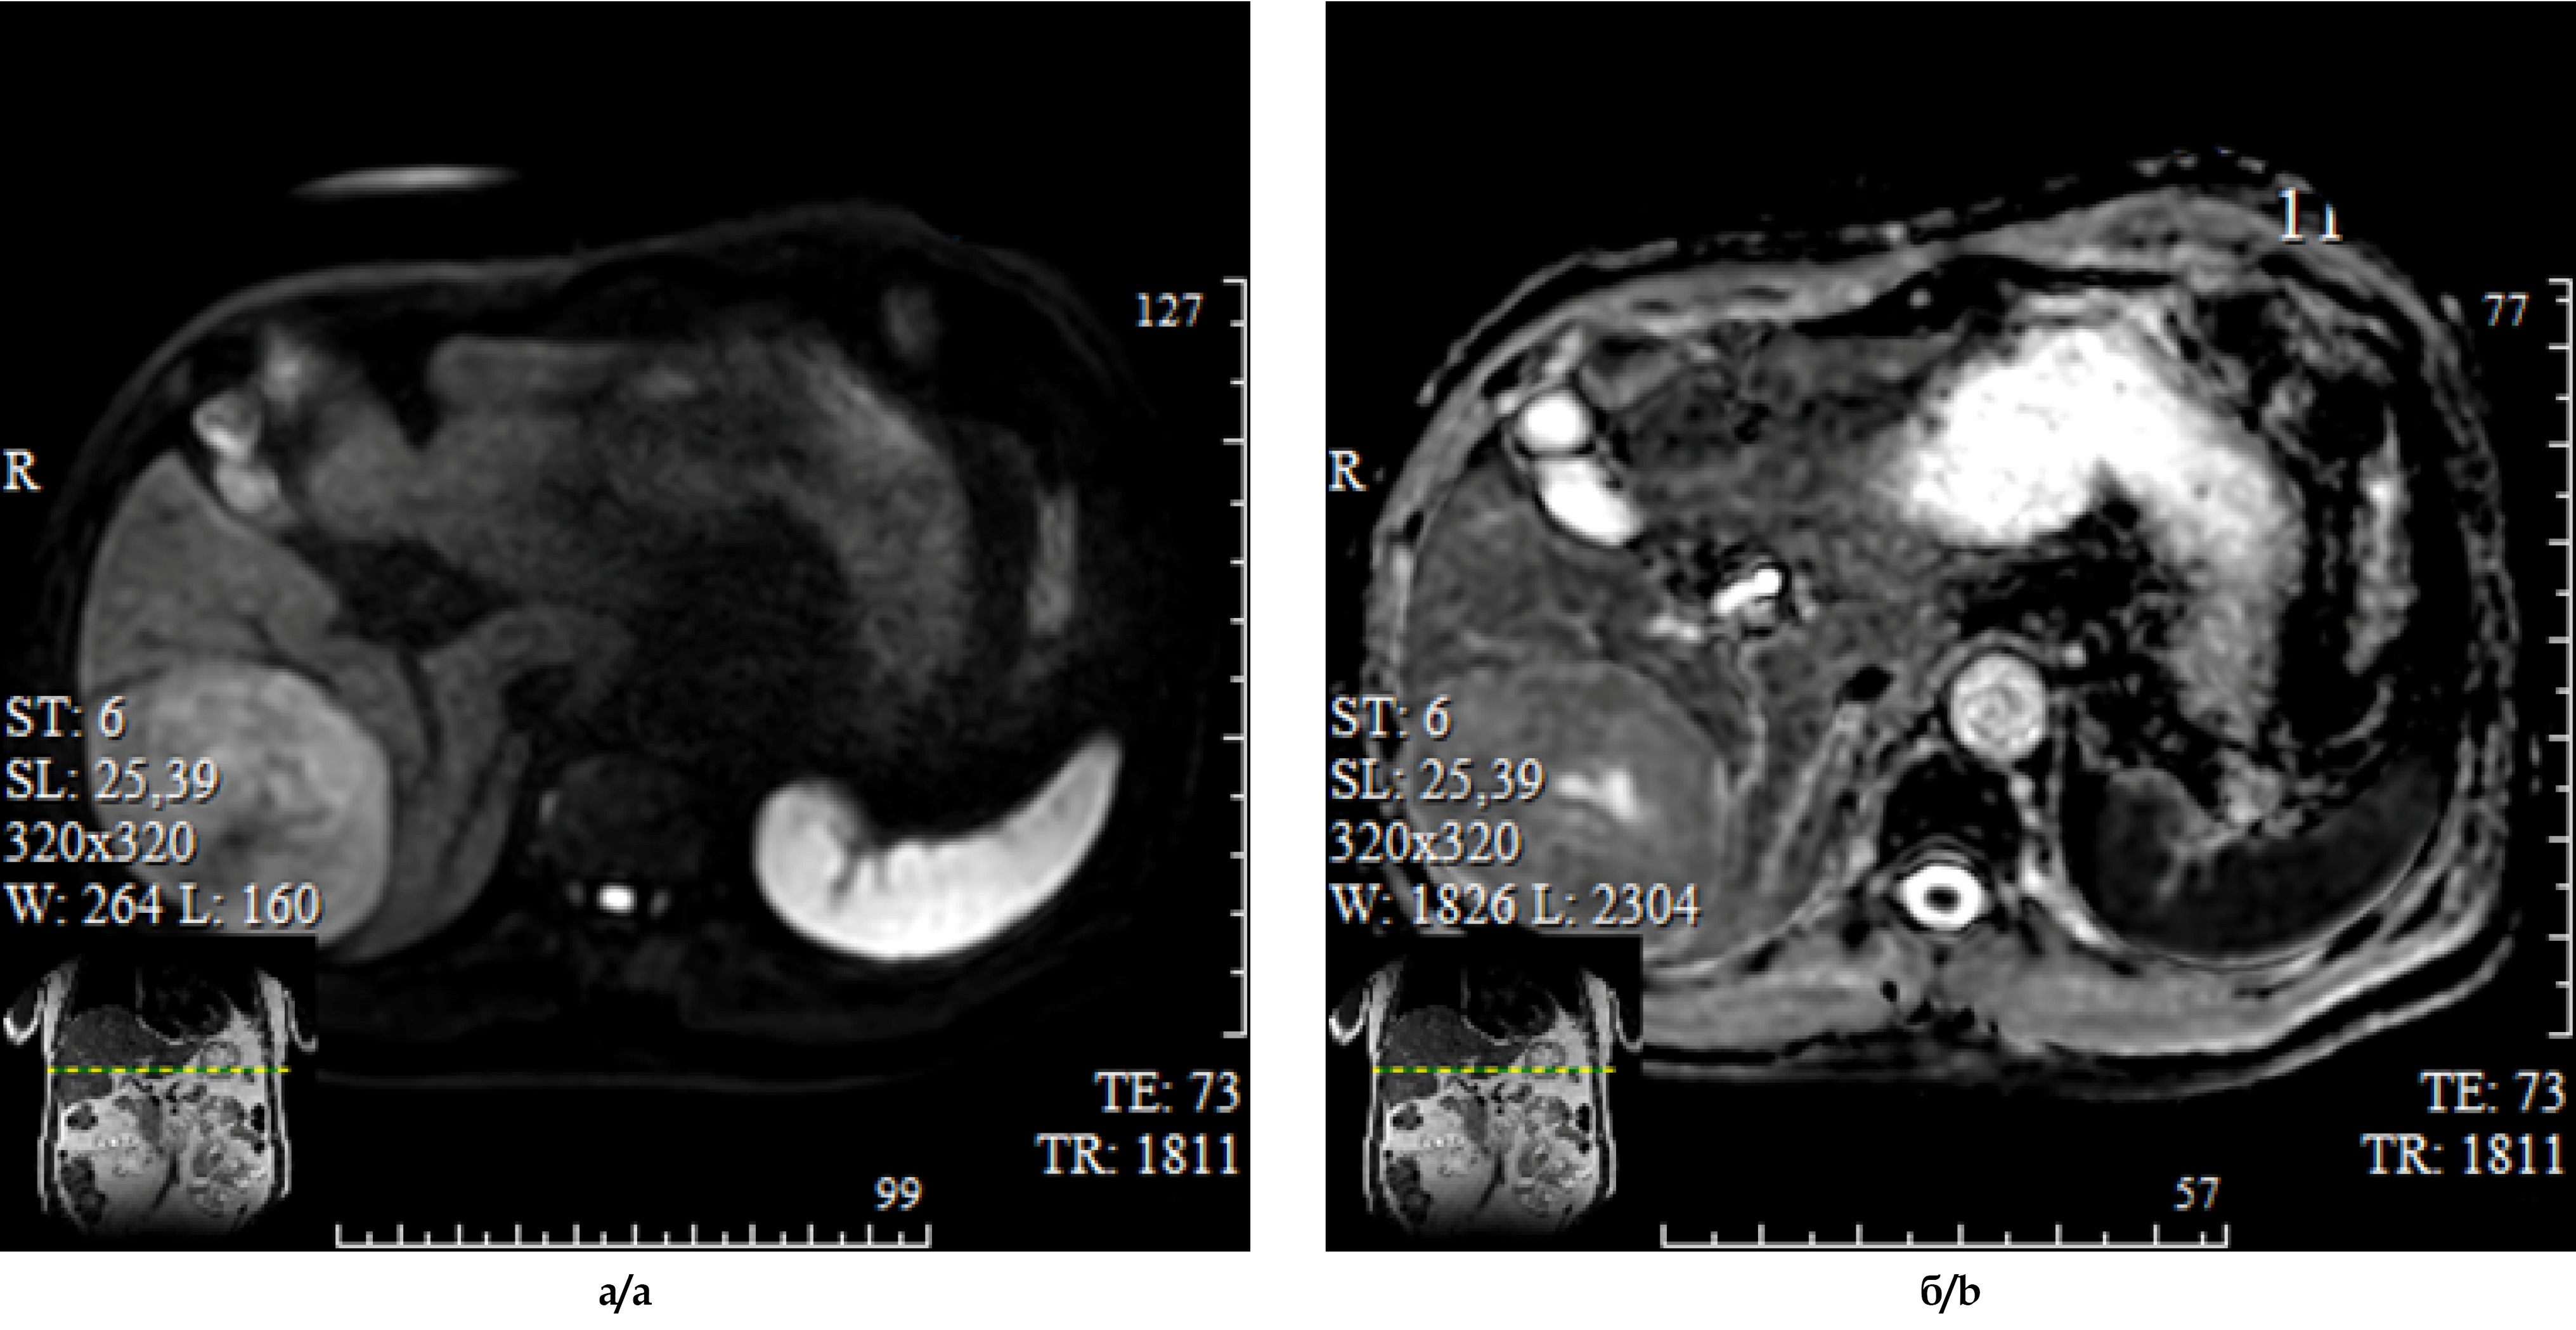

Амбулаторная консультация МСКТ-исследования. Печень пропорциональная, не увеличена, краниокаудальный размер правой доли 14 см. Контуры печени ровные, нечеткие, плотность паренхимы в нативную фазу 50 ед H (рис. 1а). В S VI, VII сегментах печени субкапсулярно визуализируется округлое образование размерами 100х80х85 мм с четкими ровными контурами (рис. 1б), гетерогенно накапливающее контрастный препарат до 115 ед. H в венозную фазу сканирования (рис. 1в). Отмечается нерезкая ретракция капсулы. Внутрипеченочные желчные протоки не расширены. Лимфатические узлы ГДС мелкие. В отсроченную фазу образование практически полностью теряет контрастное вещество (рис. 1г).

Рис. 1. МСКТ-изображения органов брюшной полости с внутривенным болюсным контрастированием: а – нативная фаза, б – артериальная фаза, в – венозная фаза, г - отсроченная фаза исследования.

Fig. 1. Enhanced Multispiral CT of the abdomen: a – unenhanced phase; b – arterial phase; c – venous phase; d – delayed phase.

Заключение. Гиперваскулярное образование S VI, VII печени может соответствовать гепатоцеллюлярной карциноме.